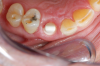

Fig 23. 12 weeks postoperatively.

Figure 23

Figure 23 showed an example of gingival soft tissue creeping occlusally and over the lingual gingival margin of the one-piece ceramic dental implant. This supragingival migration was caused by the exceptional biocompatibility due to the acid-etched surface of the implant, a one-piece implant that prevents bacterial colonization that one may find with two-piece metal-implant systems.